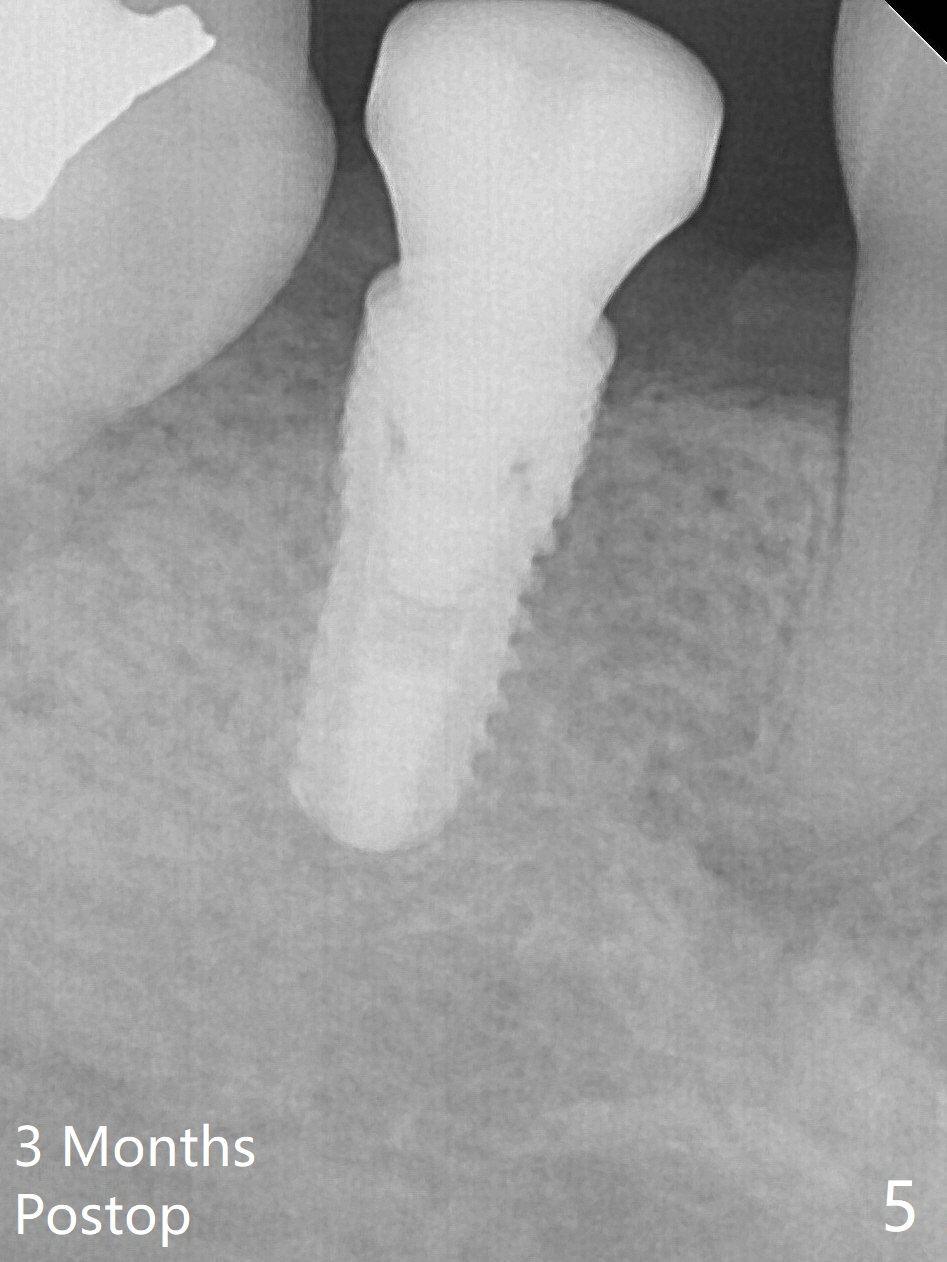

The ridge at #30 is not so narrow (Fig.1). Initial depth is 10 mm with 2 mm from the Inferior Alveolar Canal (Fig.2,3 red dashed line). A 4.5x10 mm implant is placed with > 50 Ncm; a 6.2x5(3) mm healing abutment placed (Fig.4). The implant is stable and seems to be ready for impression 3 months postop (Fig.5). CT taken 5 months post cementation shows that the implant could be placed more lingually (Fig.6 (coronal section; B: buccal)). Periradicular radiolucency at #31 (Fig.7 *) is continuous with the Inferior Alveolar neurovascular bundle (N). After extraction, care should be taken to remove granulation tissue. The tooth #32 will be extracted simultaneously because of severe bone loss.